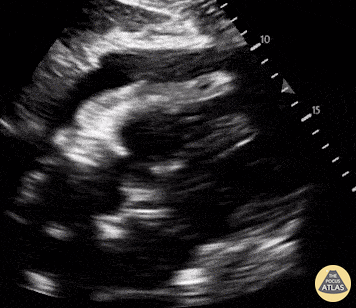

Pericardial Disease - RV Diastolic Collapse in Cardiac Tamponade

A patient with a history coronary artery disease presented to our emergency department complaining of acute weakness. He was febrile, tachycardic and hypotensive. POCUS was performed and demonstrated a circumferential anechoic rim in multiple views, consistent with a pericardial effusion (subcostal four-chamber view is shown above). Right ventricular (RV) diastolic collapse was visualized and consistent with the diagnosis of pericardial tamponade. Loss of central pulses prompted resuscitative efforts and an emergent pericardiocentesis, which resulted in return of spontaneous circulation. Andrew Namespetra, MB BCh BAO. @AndrewNamespet1 PGY-1 EM Resident at Central Michigan University Samantha Wong, DO. PGY-3 EM Resident at Central Michigan University